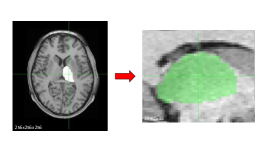

In order to reduce the time required for probabilistic tractography, we developed two types of CNNs. Looking at figure 1, the idea is to use a CNN for brain segmentation and several CNN for for direct tractography prediction. In the following we refer to the CNN which works on brain segmentations as the segmentation model, whereas the models which predict tractographies are referred to as the regression models. We have trained one segmentation model for thalamus segmentation, and six regression models (one for each cortical region considered). In this way the computational time required for tractography evaluation can be strongly reduced. However, a minimal preprocessing is still necessary: registration between structural and DWI images and DWI artifacts corrections are needed.

In this section the results obtained through the developed networks are presented and the prediction abilities of these models are quantified and discussed. First, the prediction abilities of the segmentation model and then the precentral cortex region model are illustated. An example of the comparison of the tractography maps obtained through FSL tools and the ones predicted by this model is shown in Figure 5.

Even though some differences can be noted, the predictions are similar to the true tractographies. However, in a 3D regression task it is not straightforward to quantify how much two data are similar to each other. In the next sections we report the results of the above-described evaluation methods used. Analogous models were developed and trained for other cortical regions, i.e. frontal cortex, occipital cortex, parietal cortex, postcentral gyrus, and temporal cortex, and a graphical representation is reported in Figure 6. As last step of these analyses, the thalamus can be parcelled out by using an ensemble of models.